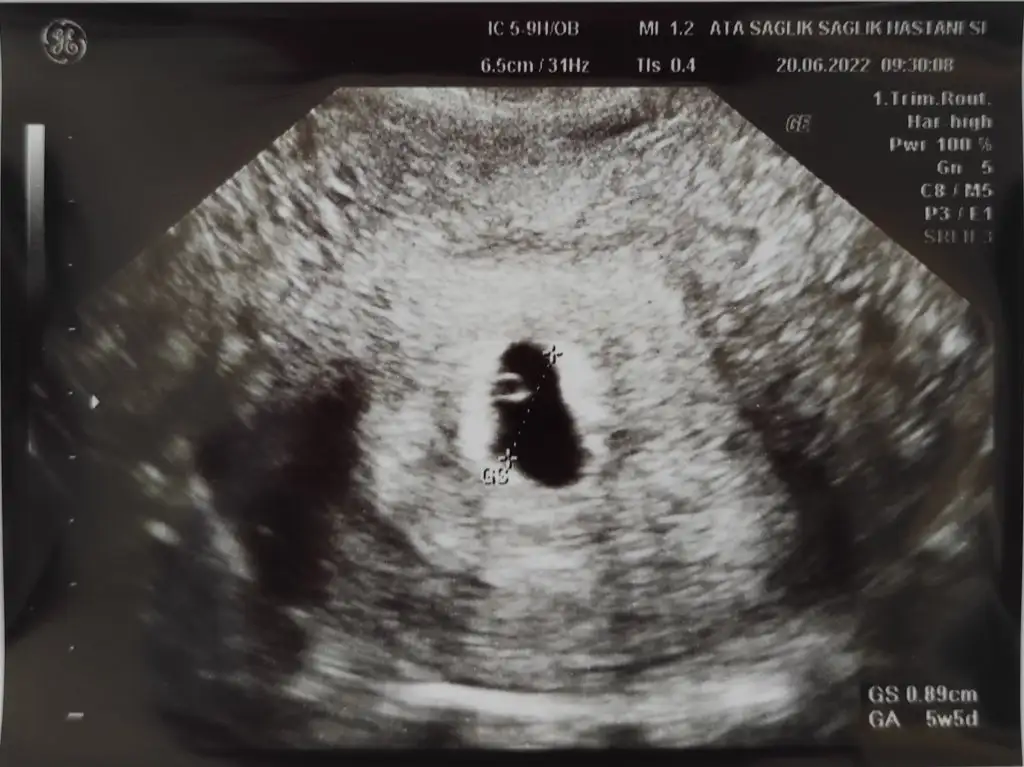

Benimkine de bakarmisiniz 8+3 karından ultrason ikiz gebelik

Eklentiler

• IMG_20220616_155146.webp

IMG_20220616_155146.webp

18,9 KB · Görüntüleme: 84

• IMG_20220616_155117.webp

IMG_20220616_155117.webp

13,8 KB · Görüntüleme: 76